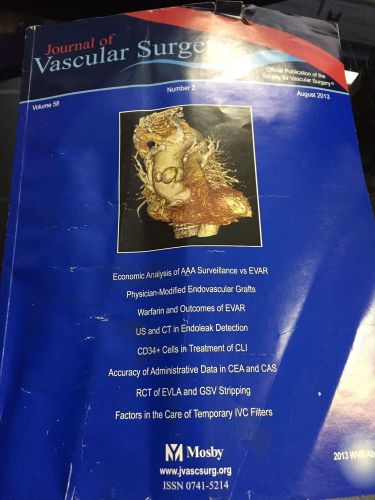

Journal of Vascular Surgery Volume 58 Number 2 p283-572 August 2013